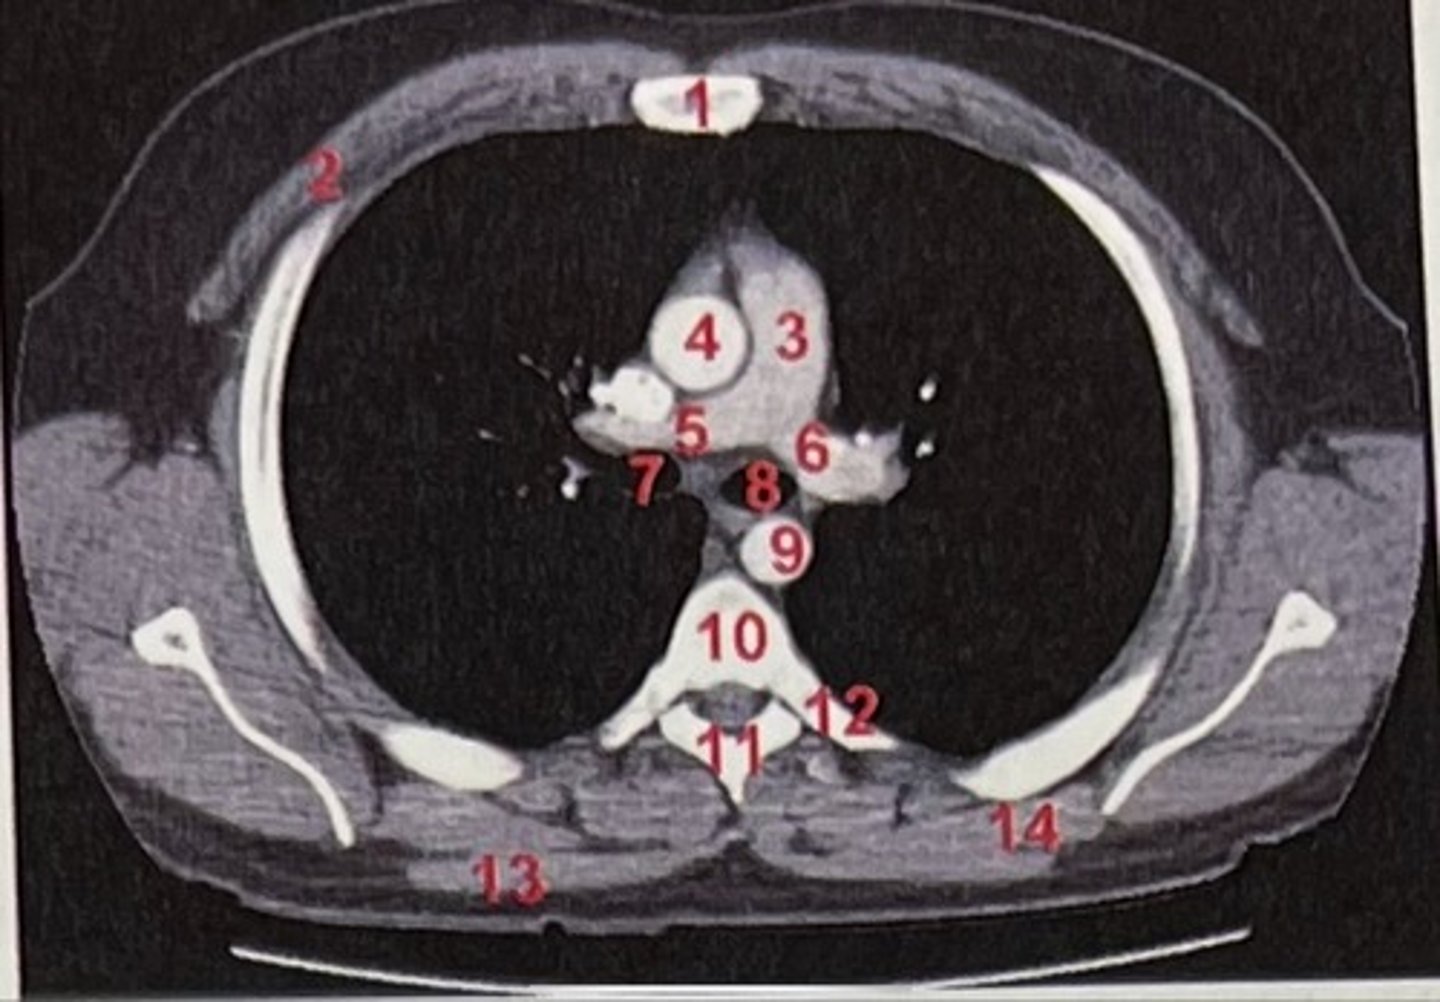

Sternum

What is 1

pectoralis major

What is 2

Pulmonary trunk

What is 3

Right and left pulmonary arteries

What is 5 and 6

Ascending aorta

What is 4

right primary bronchus, left primary bronchus

What is 7 and 8

Descending aorta

What is 9

Rhomboid major

What is 14